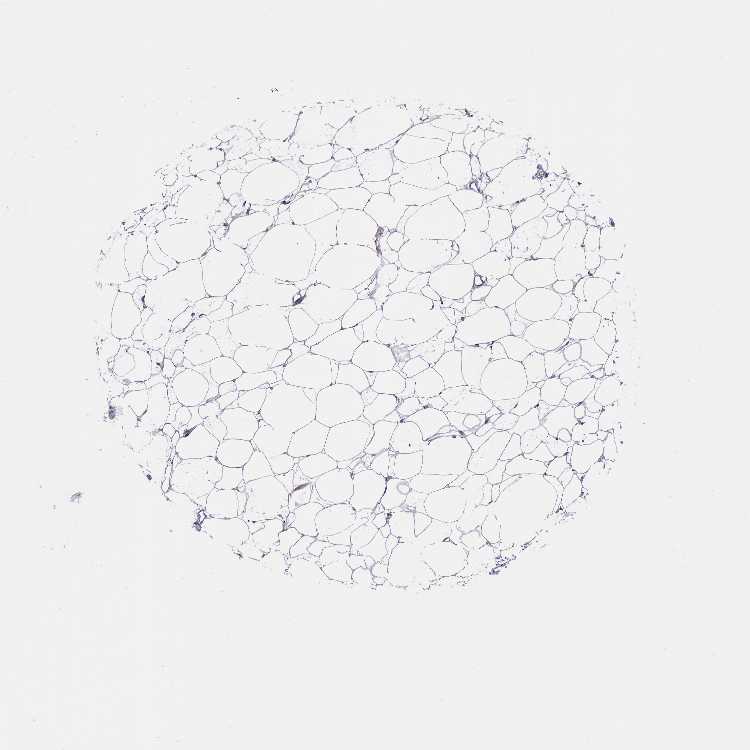

TISSUE PRIMARY DATA SOFT TISSUE Show tissue menu

SOFT TISSUE - Expression summary

SOFT TISSUE 1 - Antibody stainingi

Antibody staining in the annotated cell types in the current human tissue is reported as not detected, low, medium, or high, based on conventional immunohistochemistry profiling in selected tissues. This score is based on the combination of the staining intensity and fraction of stained cells.

Each image is clickable and will lead to virtual microscopy that enables deeper exploration of all samples and also displays staining intensity scores, fraction scores and subcellular localization as well as patient and tissue information for each sample.

Antibody HPA043249Antibody HPA048148

Chondrocytes -Medium

Fibroblasts LowNot detected

Peripheral nerve -Not detected